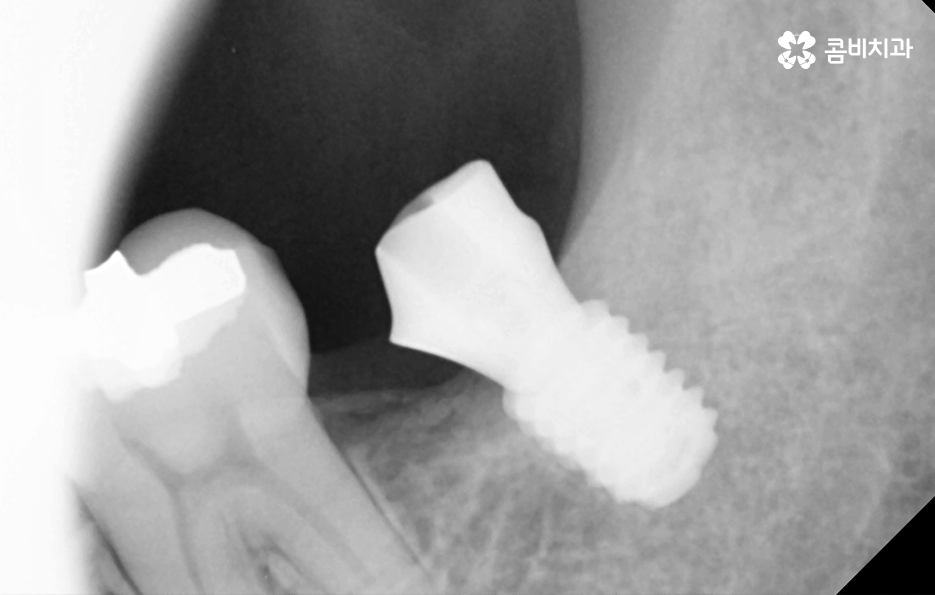

우리가 보편적으로 생각하게 되는 임플란트 치료기간의 경우 치아 하나를 상실하고 임플란트를 1:1로 치료할 때 예상 기간에 대해서 고려하게 되는 경우가 기본적인 접근 방법이라면 실질적으로 치과에서 임플란트를 하게 되는 연령대를 보더라도 보통 50대에서 60대 이후에 치아를 상실하게 되는 환자분들이 급증하기 때문에 위 사진의 사례처럼 여러 치아를 상실하고 임플란트를 식립하게 되는 경우도 많을 거예요